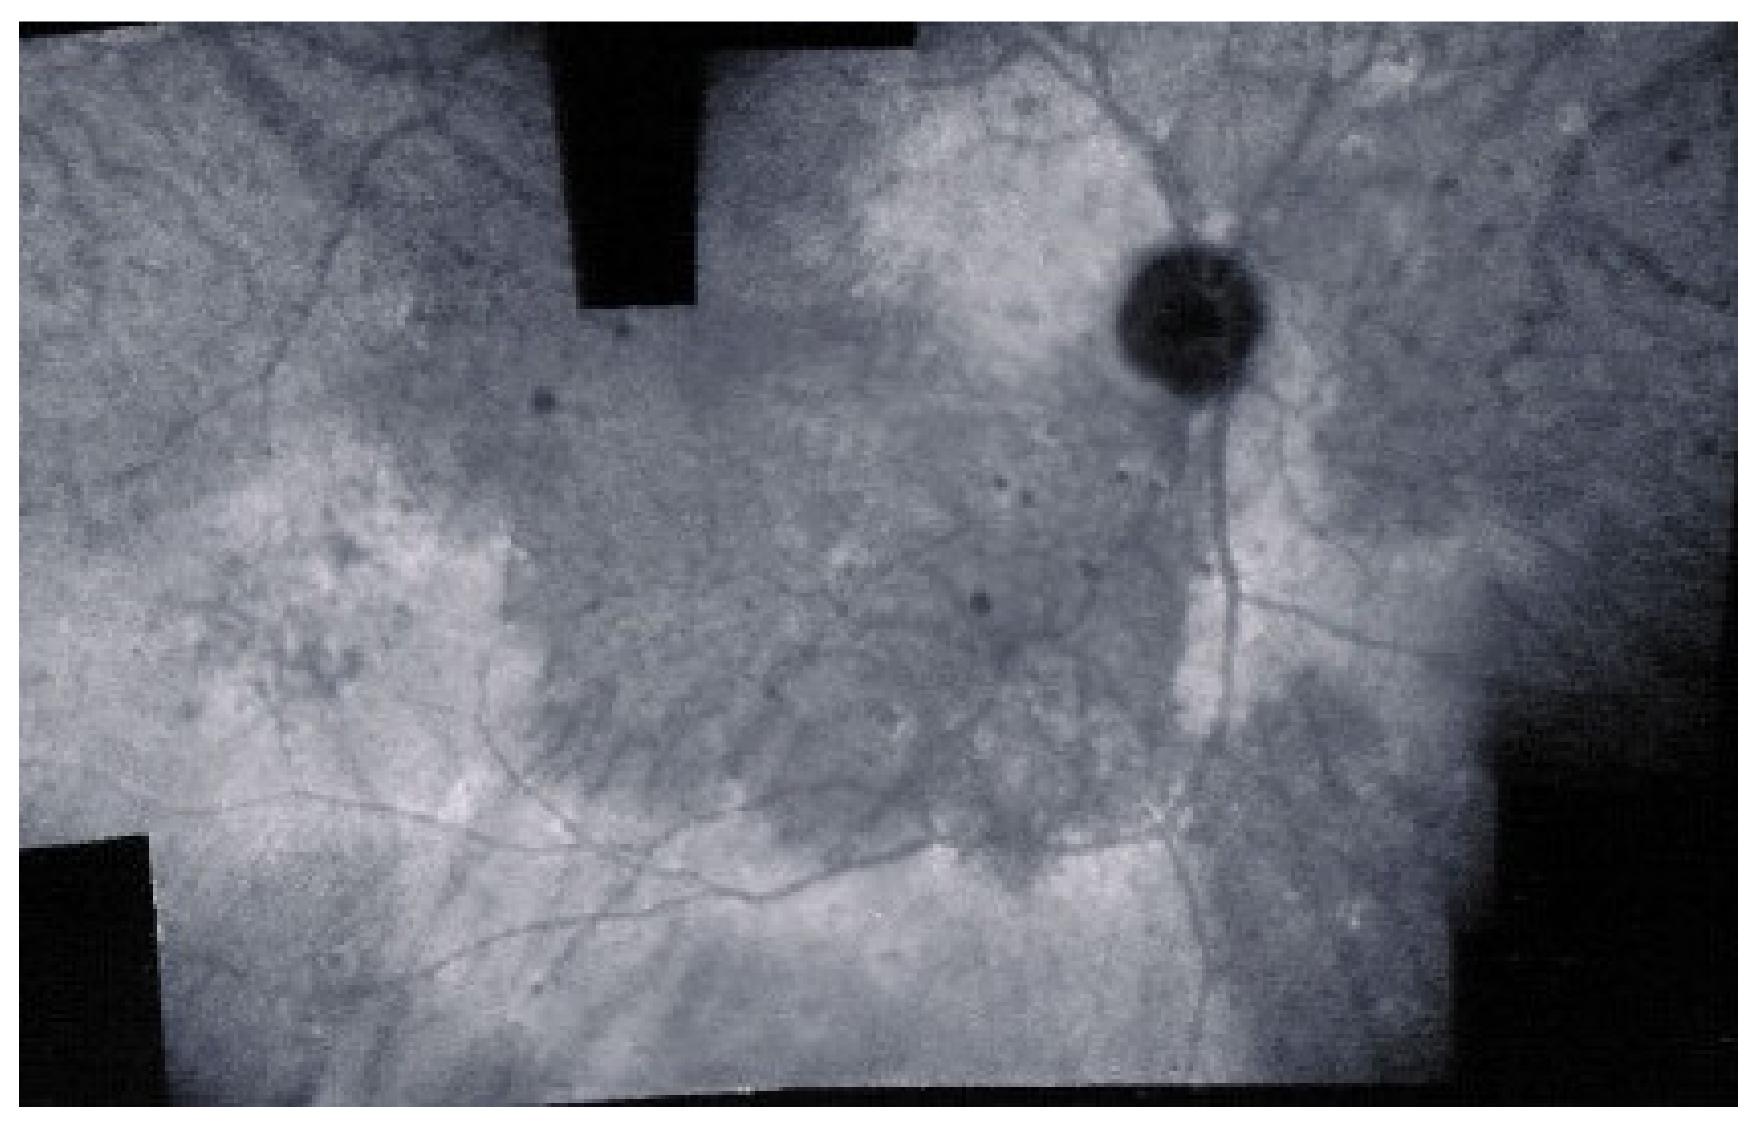

As for all PICCPs, multimodal imaging is best accounting for MFC features (Table 4). On ICGA, the first set of signs identifies old scarred chorioretinal lesions and consists of hypofluorescent areas persisting up to the late angiographic phase, distributed at random in the fundus, corresponding to late hyperfluorescence on FA, typical for chorioretinal atrophy from scars of previous inflammatory episodes seen on colour fundus photos. The second set of signs can be seen in addition to the previously described signs when choroiditis recurs or can be seen in the absence of scars when it is the first episode. The signs consist of hypofluorescent areas, either silent on fluorescein angiography or hyperfluorescent in the late phase and usually not visible on fundus examination, representing areas of new inflammatory involvement (Figure 14). As in many PICCPs, some cases may present peripapillary hypofluorescence, translating functionally into an enlarged blind spot [18,36,54,55] (Figure 15). The hypofluorescent areas can completely regress if inflammation suppressive treatment is started promptly. In a substantial proportion of cases, the extent of ICGA hypofluorescence reflecting choriocapillaris hypoperfusion or nonperfusion is far more widespread than visible lesions let suspect, showing widespread areas of late occult hypofluorescence with absolutely no signs visible on fundus examination or on fluorescein angiography (Figure 15).

Subretinal neovascular membranes occur in up to ¼th of cases. ICGA of old lesions shows mainly hypofluorescent areas up to the late angiographic phase, indicating chorioretinal scarring and atrophy [4]. In areas of active disease progression, ICGA shows hypofluorescent areas that go beyond the lesions seen on fundoscopy and/or fluorescein angiography (Figure 24). Another ICGA sign that can give information on disease activity is a diffuse perilesional hyperfluorescence [30] (Figure 24).